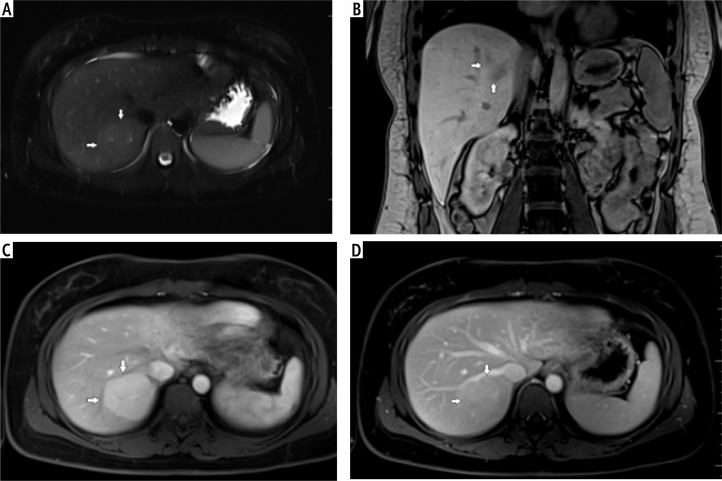

Aim of the study: Hepatocellular adenoma (HCA) and focal nodular hyperplasia (FNH) are benign liver tumors. Hepatocellular adenoma has potential for growth, metaplasia and rupture; therefore, it should be monitored long term. In the current guidelines biopsy is not recommended in the standard diagnostic protocol. Magnetic resonance imaging (MRI) is accepted as standard in diagnostics and monitoring of these lesions. The aim of the study was to compare contrast-enhanced ultrasound (CEUS) and MRI in imaging of these tumors and determine whether CEUS can be useful in monitoring benign liver tumors.

Material and methods: A retrospective analysis of 47 patients with HCA (32 tumors) and FNH (27 tumors) was carried out. A comparison between MRI and CEUS in predicting malignant transformation was performed.

Results: A similar tumor enhancement profile to unchanged liver parenchyma was observed in both groups. The difference in the arterial phase was on average up to 30 dB. After 20-30 s, the enhancement of HCA and FNH in relation to the liver parenchyma was similar (difference up to 4-5 dB). Homogeneity and equalization of the tumor to background enhancement was observed until the end of the examination. The discriminative feature is the presence of a non-contrasting central fibrous scar observed in both imaging methods in the FNH group.

Conclusions: CEUS can be a promising method in monitoring focal liver lesions due to low cost and low risk of complications. It is essential to analyze the early arterial phase up to 30 s to demonstrate homogeneous enhancement of the tumor and potential presence of a wash-out effect during later phases of examination.